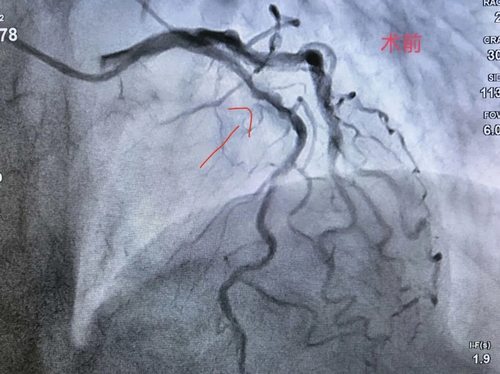

患者曾某某,女性,72岁,一个月前因急性心肌梗死入院。急诊造影显示:前降支、右冠重度狭窄伴严重钙化,回旋支完全闭塞。心血管病科团队第一时间开通闭塞的回旋支并植入支架,患者转危为安。

本次为行二期治疗,患者再次入院,拟对前降支及右冠进行处理。术中造影提示,前降支重度狭窄且钙化极为严重。血管内超声进一步提示:前降支存在270°范围的弥漫性长节段钙化——这意味着血管壁坚硬如石,常规球囊根本无法充分扩张,支架也无法良好贴壁,是介入治疗中公认的"硬骨头"。